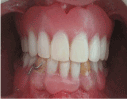

Intra-oral examination (Figure 4) revealed mixed dentition in her oral cavity. Teeth were

Figure 4. Oral cavity after improving oral hygiene and before  starting surgical exposure and orthodontic treatment.

The patient has poor oral hygiene, points of bleeding, but no pockets more than 3mm or tooth mobility.

No supernumerary teeth. The patient had skeletal class III malocclusion. The radiograph demonstrated that the upper anterior teeth were  close to the gingival margin, and so the lower anterior teeth. After improving the oral hygiene and periodontal condition, consultation with the orthodontic department about the possibility of orthodontic treatment after surgical exposure of the impacted teeth. As the impacted teeth in more than one sites so surgical exposure was performed in more than one visit and orthodontic traction of the impacted teeth was started by powerful unity anchorage.